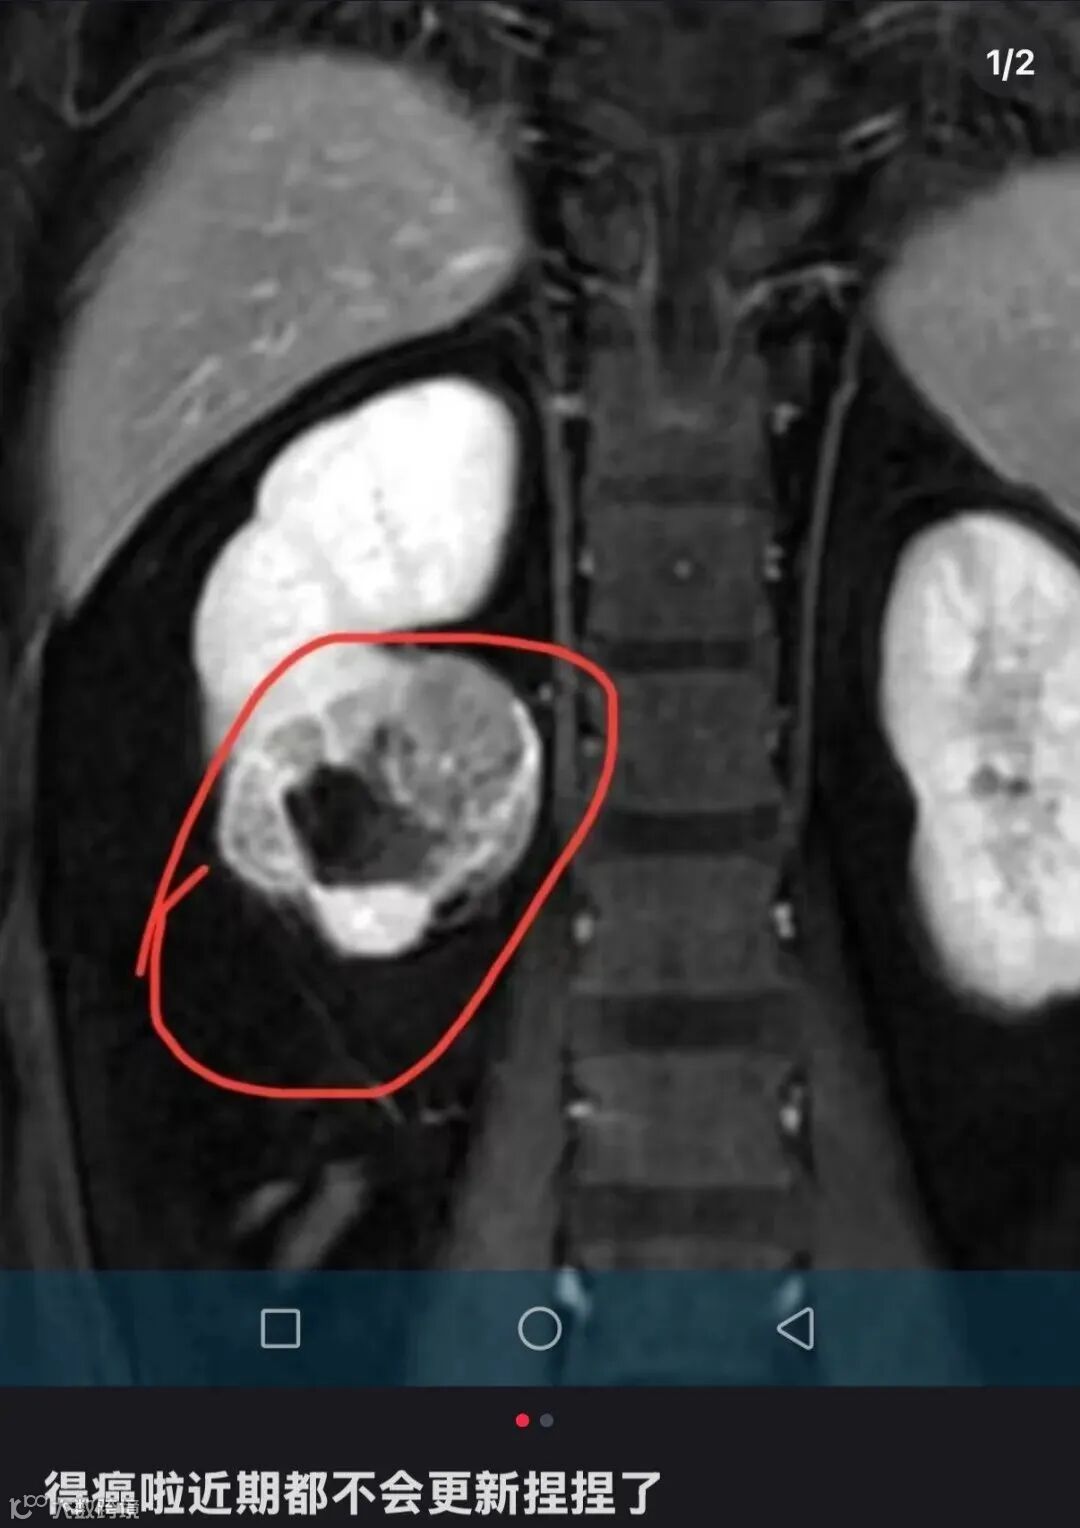

近两年,一种装在透明袋子里的“捏捏”,成为年轻人缓解压力的热门选择。近日,一位ID名为“有只猫叫小朋友”的捏捏博主发文告诉粉丝:“得癌了,近期都不会更新捏捏了。”博主公开了自己的诊断病例,显示诊断意见为“右肾下级占位,肾CA可能,建议穿刺活检。”意味着医院给出的诊断是右肾下极区域出现异常组织占据,存在肾细胞癌的可能,让解压玩具捏捏致病问题,再度成为热议话题。

该博主在社交平台宣布罹患癌症。图源其账号截图